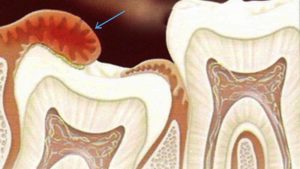

- Разрушение соседнего зуба, который вызывает дополнительные болевые ощущения;

При перикороните, связанном с прорезыванием «восьмерок», очень часто встречается дистопия. Это аномалия, при которой зубы занимают неправильное положение в челюстной дуге (наклонены в стороны, вперед, назад) или же появляются за ее пределами. Дистопированные зубы прорезываются с трудом и, как правило, мешают прорезываться своим соседям.

- болезненность и разрушение соседнего зуба при неправильном положении зуба мудрости во время прорезывания;

Регионарные лимфатические узлы сильно увеличены, из-за боли и отечности воспаленных тканей десны, щек, мягкого неба и небно-язычной дужки пациент не может открыть рот. Если надавить на десневой капюшон, из-под него выдавливается гнойный экссудат. Рентгенологическое исследование позволяет обнаружить рассасывание костной ткани в области зуба мудрости.